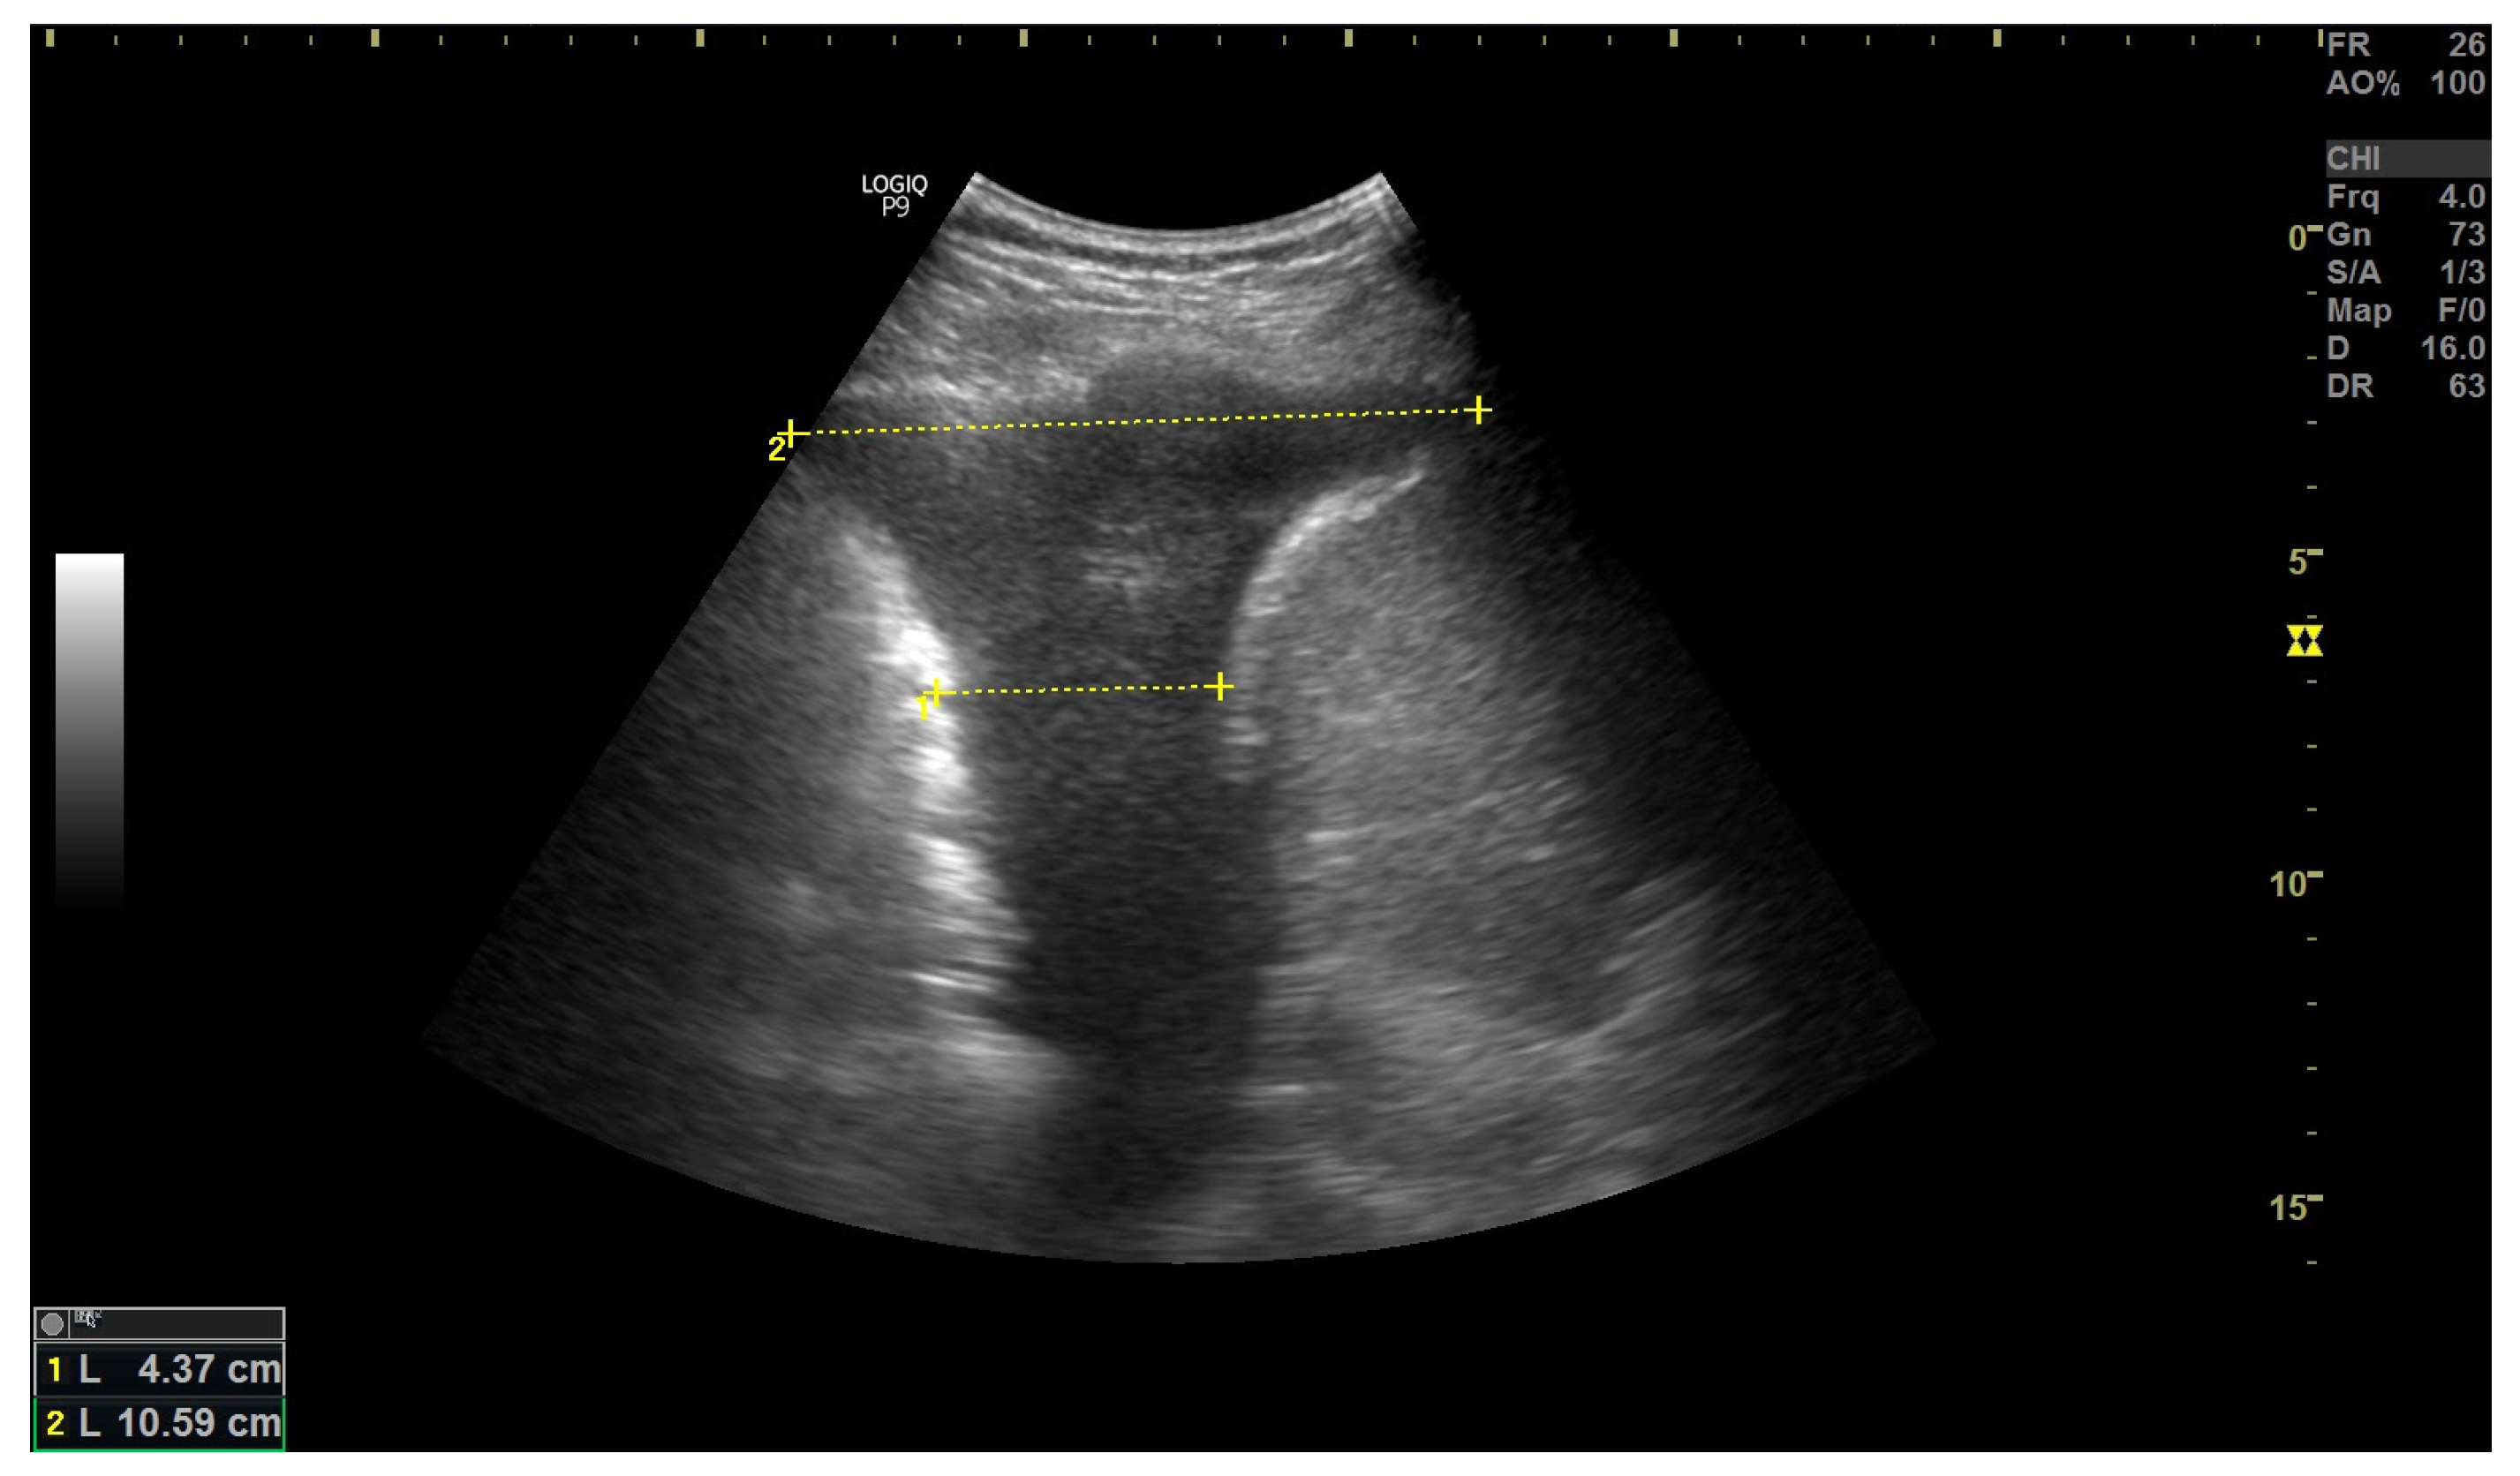

3.2. Inferior Vena Cava Measurement

- Yamanoğlu, A.; Çelebi Yamanoğlu, N.G.; Parlak, İ.; Pınar, P.; Tosun, A.; Erkuran, B.; Akgür, A.; Satılmış Siliv, N. The Role of Inferior Vena Cava Diameter in the Differential Diagnosis of Dyspneic Patients; Best Sonographic Measurement Method? Am. J. Emerg. Med. 2015, 33, 396–401. [Google Scholar] [CrossRef] [PubMed]

- Blehar, D.J.; Dickman, E.; Gaspari, R. Identification of Congestive Heart Failure via Respiratory Variation of Inferior Vena Cava Diameter. Am. J. Emerg. Med. 2009, 27, 71–75. [Google Scholar] [CrossRef]

- Kajimoto, K.; Madeen, K.; Nakayama, T.; Tsudo, H.; Kuroda, T.; Abe, T. Rapid Evaluation by Lung-Cardiac-Inferior Vena Cava (LCI) Integrated Ultrasound for Differentiating Heart Failure from Pulmonary Disease as the Cause of Acute Dyspnea in the Emergency Setting. Cardiovasc. Ultrasound 2012, 10, 49. [Google Scholar] [CrossRef]